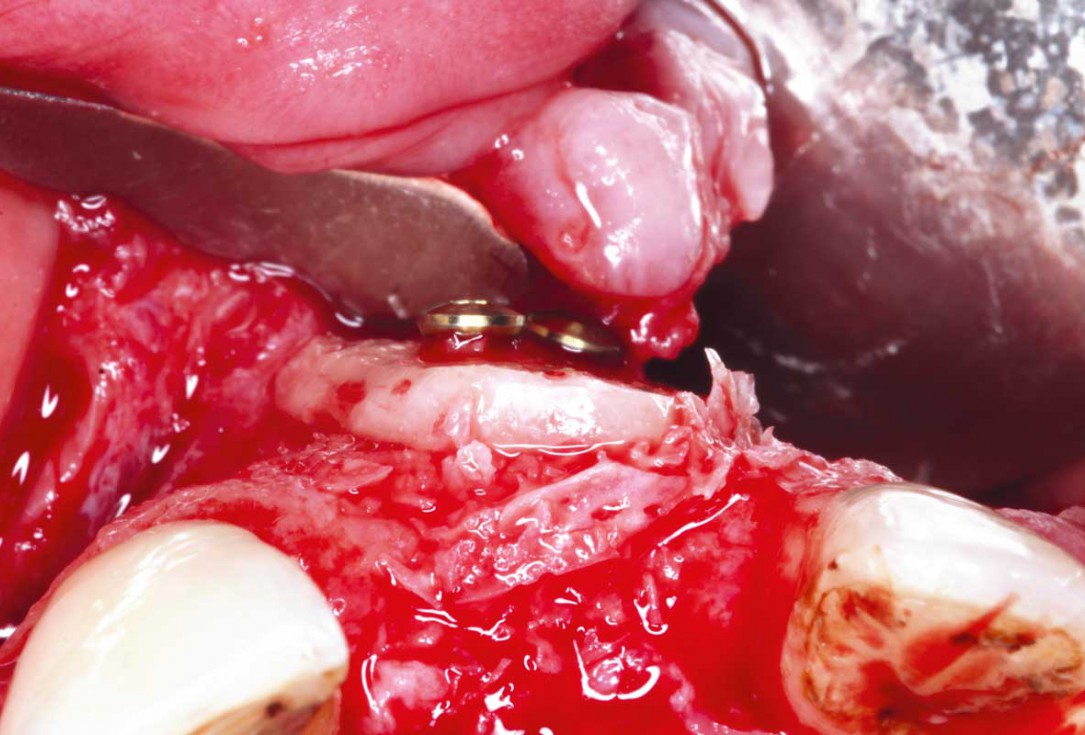

9/35 - Stabilisation of the bone block with two 10 mm fixation screws placed oblique. Sharp edges of the block were polished to avoid defeasance in the soft tissue healingBlock grafting in the aesthetic zone with maxgraft®, Jason® membrane and cerabone® - Dres. H. Maghaireh and V. Ivancheva

10/35 - Stabilisation of the bone block with two 10 mm fixation screws placed oblique. Sharp edges of the block were polished to avoid defeasance in the soft tissue healingBlock grafting in the aesthetic zone with maxgraft®, Jason® membrane and cerabone® - Dres. H. Maghaireh and V. Ivancheva